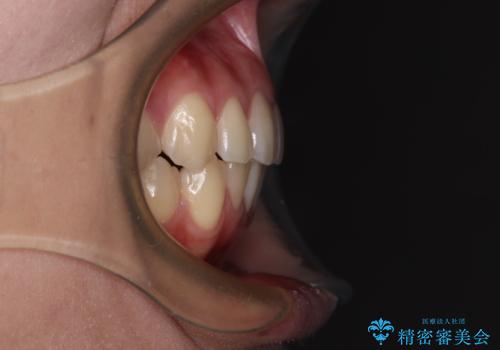

抜歯するほどではないものの、やや口元の突出感が気になっていたので、補助装置により上顎臼歯を後方に移動させることで、突出感改善を図ることとしました。

1年弱の短期間で、望み通りのスッキリとした口元に仕上げることができました。